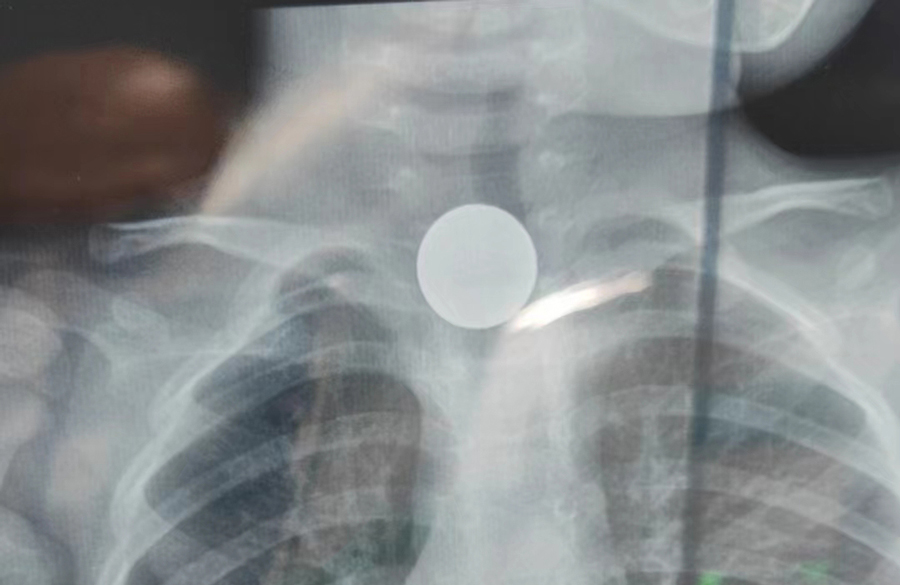

小强(化名)是27月龄的小男孩,活泼好动,家住长春市。小强妈妈说,儿子反复发热一个月了,还出现吞咽困难和呕吐症状,也没有以前活泼了,吃得少,到最后只能喝点水和奶。家人没太重视,以为感冒了,胃口不好,自行购买各种感冒药给小强服用,但孩子的症状始终得不到缓解。在来我院就诊的前一天,他们因为“肺炎”带孩子在其他医院就诊,医生检测时发现其食道入口处有金属异物,建议他们赶紧到儿童医院进行治疗。

了解了患儿的情况后,国家儿童医学中心、首都医科大学附属北京儿童医院耳鼻喉头颈外科常驻专家、蜜桃视频 副院长张薇仔细看了患儿的X光片,明确了异物的存在和准确位置。由于异物存留时间长,食道是否有肉芽增生、有无穿孔等情况都不明确,张薇副院长决定采用全麻下通过食道镜直视下行异物取除术。